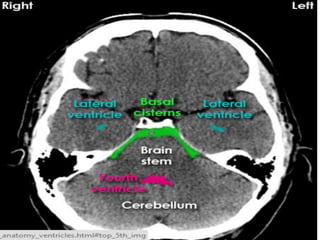

• Ventricles symmetry and cisterns any

effacement.

Disoders of CSF spaces

Approach to theCT • Look parenchyma for hypodensities ,hyperdensities, their location, shape, homogenous/heterogenous,any mass effect or odema. • Grey-white matter differentiation, any enhacement if contrast film. • Ventricles symmetry and cisterns any effacement.